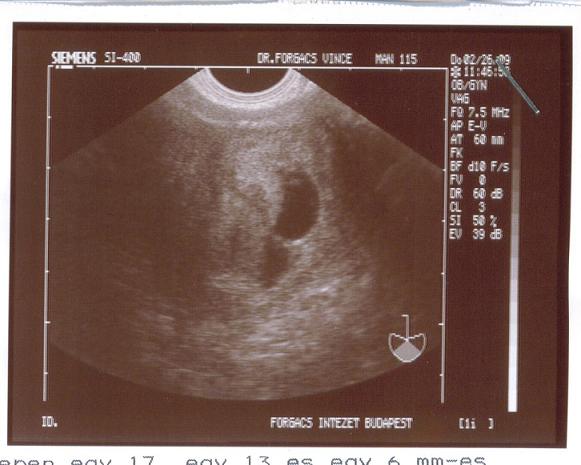

BPD:99mm

Fl: 74mm

AC: 351

Bs: 3900gr

TErmészetesen szülhetek el se hiszem, biztonság kedvéért kaptam szerdára időpontot de doki és szülésznéni is úgy érzi a vizsgálat alapján, hogy talán 2-3 napon belül gyerek lesz, mert a fájások állandóak .